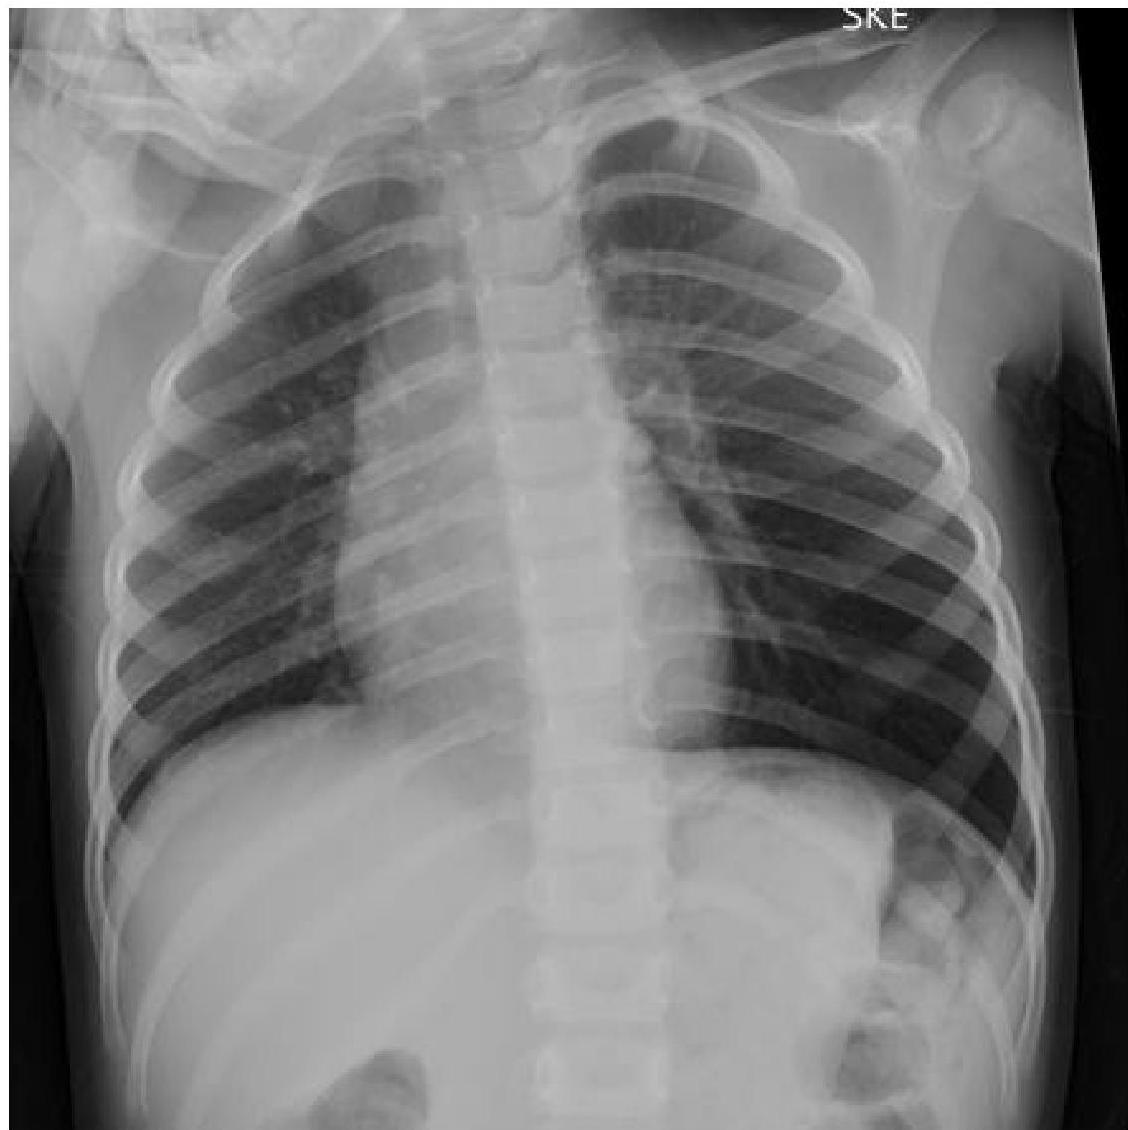

foreign body aspiration deep sulcus - diaphragm depressed